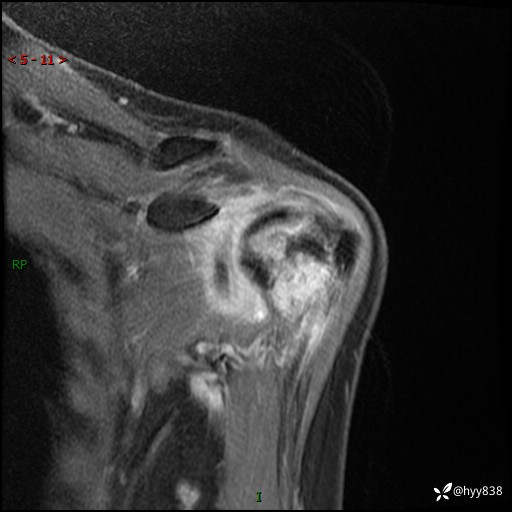

肱骨MRI平扫(axi T1WI+cor T2WI-fs)+CE-fs(COR+SAG)